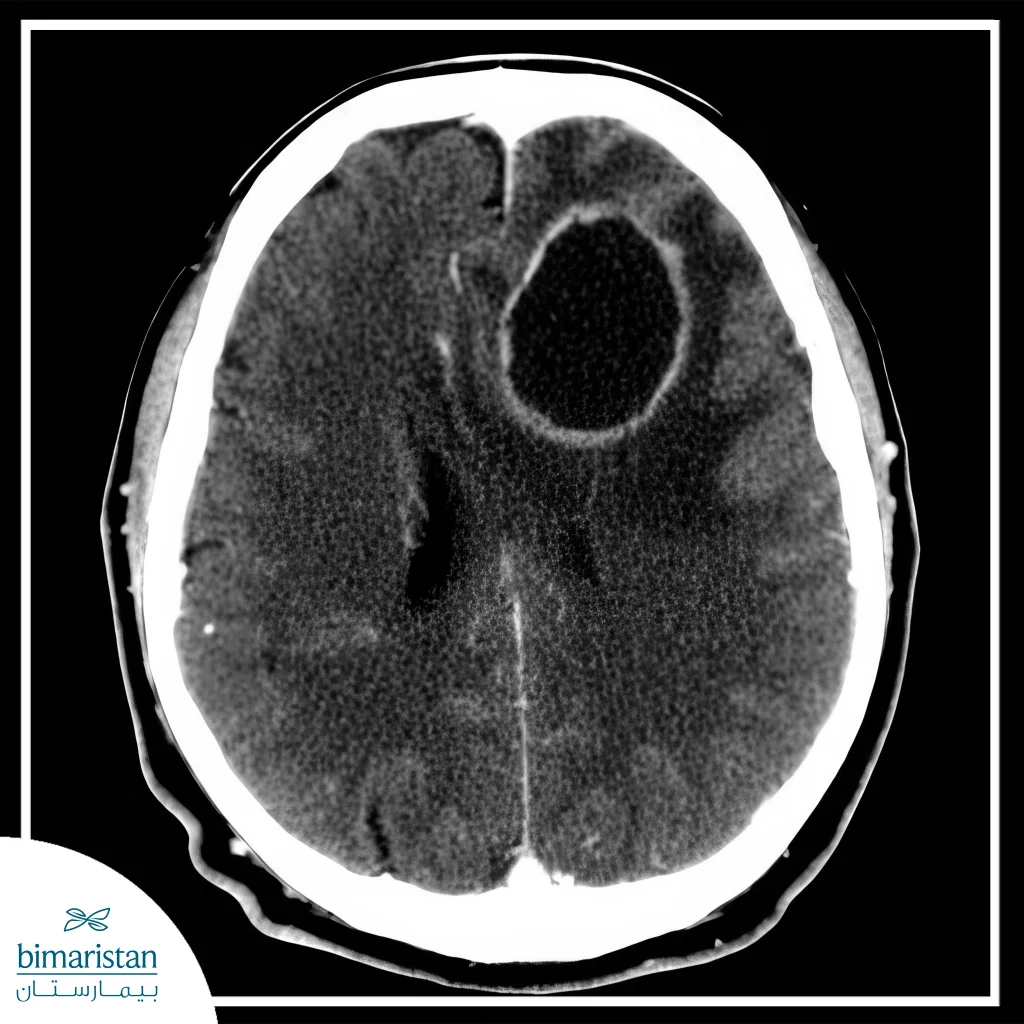

A brain abscess is a purulent collection of pus within the brain tissue, resulting from a bacterial, fungal, or parasitic infection. Although it is considered a rare condition, it is an emergency that requires immediate medical intervention to prevent complications that may be life-threatening.

The size of brain abscesses varies according to the type of infection, ranging from very small to large abscesses that exceed 3 cm. Large abscesses require surgical intervention to drain them, as they cause pressure on the brain and serious displacement that may be life-threatening.

In addition to that, abscesses near the ventricles are an emergency warning sign that requires emergency surgical intervention, because they can rupture and cause ventriculitis, an inevitably fatal condition if not treated. Brain abscess surgery may be necessary in cases of multiple abscesses, especially if they are large or in critical areas.